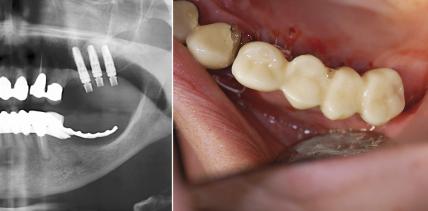

Webinar: Implantologische Sofortversorgung mit Xive

Dr. Martin Christiansen, M.Sc. stellt ein intelligentes und sicheres Konzept zur Sofortversorgung von Implantaten vor. Der erfahrene Implantologe referiert... Dr. Martin Christiansen, M.Sc. stellt ein intelligentes und sicheres Konzept zur Sofortversorgung...